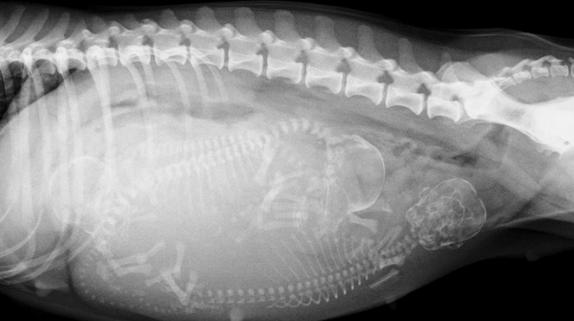

有经验的兽医通过轻轻触摸猫咪的腹部可以在怀孕17-25天时摸到怀孕后子宫内出现的孕囊。但更精确的判断就需要拍摄X线片及做B超检查了哦。

约在怀孕43-45天后拍摄X线片可以明显的看到小猫的骨骼~(请放心这时的X线片是不会对怀孕猫咪及小猫造成伤害的)。而约20天时,通过B超检查探测到的小猫心脏的跳动也是它们在告诉你“我很好~!请不要担心我!”